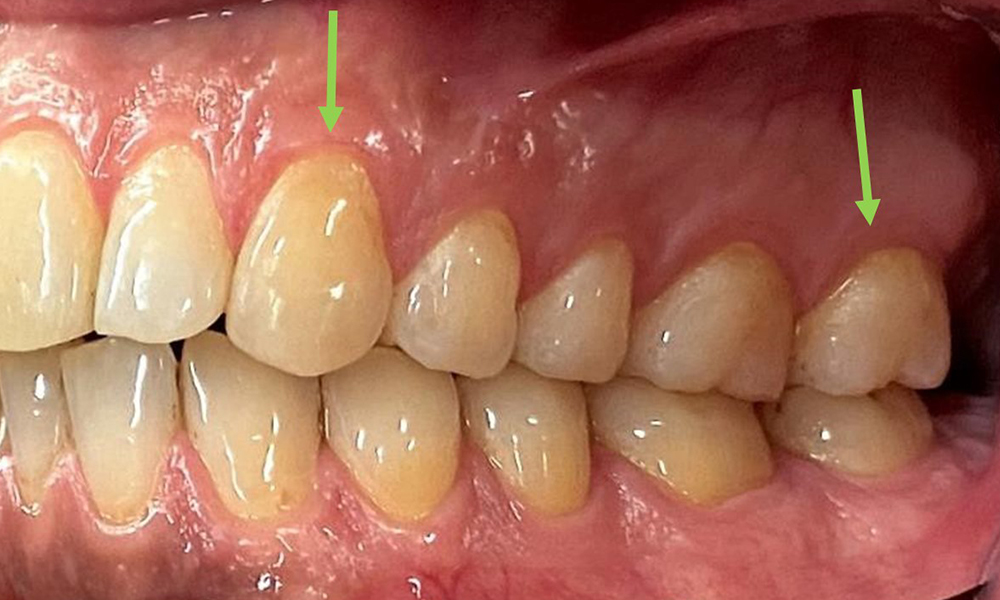

Extraoral sind keine pathologischen Befunde festzustellen, intraoral zeigen sich bei der Frontalansicht im Bereich der keratinisierten Gingiva und am Übergang zur beweglichen Schleimhaut bräunlicheVerfärbungen (Abb. 2), welche auf den Nikotingenuss zurückzuführen sind. Am Gaumenbereich zeigen sich insbesondere im Bereich Oberkiefermolaren palatinal weißliche Schleimhautveränderungen, die ein Hinweis auf einen erhöhten Verhornungsgrad sind und ebenso auf den Nikotingenuss zurückzuführen sind. Die Zunge ist mit einem weiß-bräunlichen abwischbaren Belag versehen.

Dental zeigt sich ein vollbezahntes Gebiss mit 28 Zähnen. Auffällig sind Erosionen und Attritionen

(Abb. 4, Abb. 5). Der Patient trägt seit vielen Jahren nachts eine Schiene mit adjustiertem Aufbiss aufgrund Bruxismus. Die Erosionen sind auf den langjährigen Konsum isotonischer Getränke zurückzuführen. Parodontaler Knochenverlust und aktive kariöse Läsionen sind nicht vorhanden.

Die klinischen Sondierungstiefen liegen mit 1-3mm im physiologischen Bereich. Im Oberkiefer zeigen

sich von 13-16 sowie 23-27 Rezessionen bis 1mm. Der BOP liegt bei 15%.

Nahaufnahme der Zähne

Abb. 5: Nahaufnahme der Zähne 45-47. Grüne Pfeile zeigen Attritionen und Erosionen im Bereich der bukkalen Höcker mit partiellem Schmelzverlust, © Dr. R. Krapf